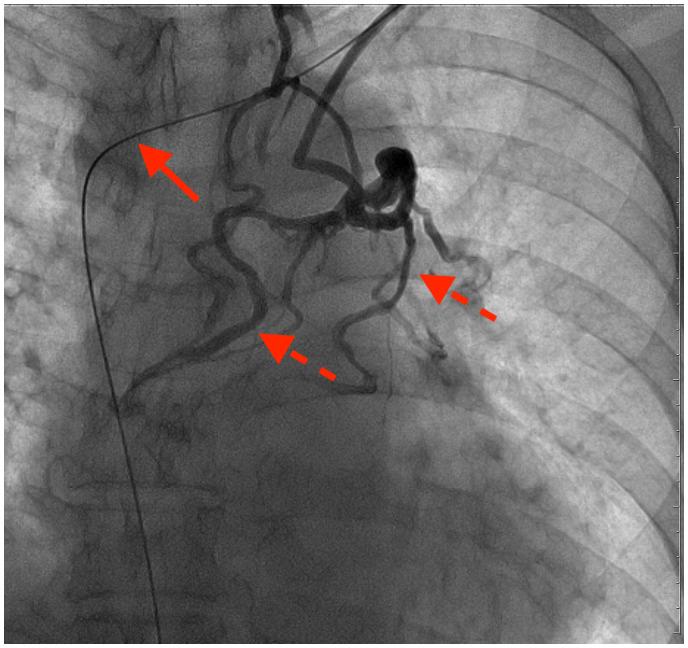

A 68-year-old man who had experienced dyspnoea on exertion by c-AVB was admitted to our hospital for treatment and management. Permanent pacemaker insertion was initially planned; however, an endocardial pacemaker lead could not be implanted in the right atrium. Computed tomography scan with contrast revealed that the venous blood from the upper half of the body flowed into the inferior vena cava via the azygos vein. Due to the difficulty of inserting an endocardial lead from the subclavian vein, a leadless pacemaker (LP) was implanted instead via the femoral vein.

一名68岁男性因c-AVB导致劳力性呼吸困难入院接受治疗和管理。最初计划植入永久性起搏器;然而,无法将心内膜起搏器导线植入右心房。增强计算机断层扫描显示,来自身体上半部分的静脉血通过奇静脉流入下腔静脉。由于从锁骨下静脉插入心内膜导线困难,改为通过股静脉植入无导线起搏器(LP)。